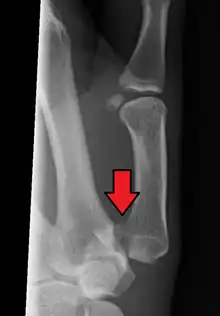

| Bennett fracture on x-ray | |

Bennett fracture is a type of partial broken finger involving the base of the thumb, and extends into the carpometacarpal (CMC) joint.[1]

This intra-articular fracture is the most common type of fracture of the thumb, and is nearly always accompanied by some degree of subluxation or frank dislocation of the carpometacarpal joint.

Though these fractures commonly appear quite subtle or even inconsequential on radiographs, they can result in severe long-term dysfunction of the hand if left untreated. In his original description of this type of fracture in 1882, Bennett stressed the need for early diagnosis and treatment in order to prevent loss of function of the thumb CMC joint, which is critical to the overall function of the hand.[4]